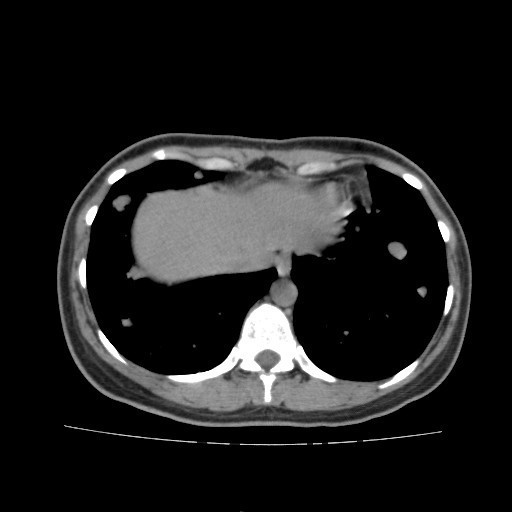

查体:右大腿上段较左侧增粗,后内侧皮下可触及大小约5*6cm肿物,质软,边界不清,活动度可,压痛(+),无波动感。 辅助检查:胸部CT:双肺多发转移瘤。

诊断:肺占位性病变(转移瘤?);大腿软组织疾患(右侧大腿肿物) 治疗:入院右下肢MR平扫+增强扫描:右侧大收肌软组织占位性病变,考虑间叶源性恶性肿瘤可能性大,血管源性可能?瘤周多发静脉曲张及侧枝循环形成,建议CT增强扫描进一步检查明确血管情况。遂于声引导下右大腿肿物穿刺活检,病理结果提示:(右大腿肿物)送检穿刺组织,肿瘤细胞形成器官样及腺泡状结构,细胞巢间为纤维性分隔,细胞呈大圆形、多边形,胞质丰富透亮,部分呈嗜伊红色,细胞核大,核分裂象少见,结合临床病史及免疫组化,考虑为腺泡状软组织肉瘤。免疫组化结果(①):CK(-),Vim(-),Ki-67(5%+),HMB45(-),MelanA(-),SMA(+),desmin(-),Myogenin(-),MyoD1(-),S100(-),NSE(部分+),CD56(-)。